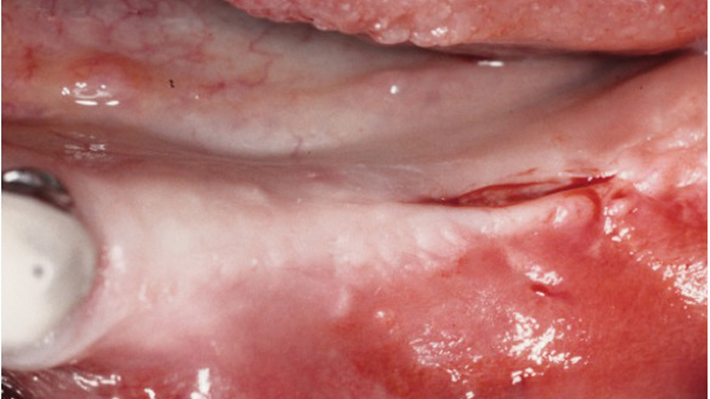

“Thin ridge expansion with minimally invasive surgery!

Use SmarThor & AnyRidge to place a wider diameter implant with minimal drilling after ridge splitting, even in thin ridge under 2mm! “

Clinical case: Ridge splitting technique using SmarThor + AnyRidge as expander

- Courtesy of Dr.Kwang-Bum Park, Korea -

Keywords

AnyRidge, ridge splitting, GBR, Dr. Kwang-Bum Park, mandibular posterior, SmartThor, Mega-Oss, thin ridge, bone regeneration

Products:

AnyRidge implant system. SmarThor, Mega-Oss